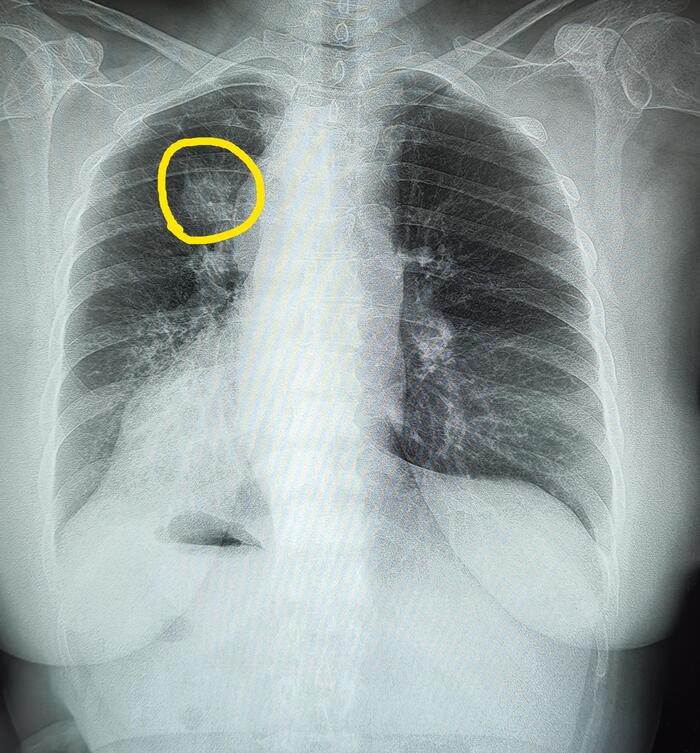

Справа по парастернальной линии, чаще на уровне 1-го межреберья (иногда на уровне хрящевой части 1 или 2-го ребер) определяется небольшая в форме вытянутой капли тень (от 0,3 до 0,8 мм ширины и от 0,6 до 2,5 мм длины) с четкими контурами. Эта «капля», заостряясь кверху, переходит в нежную (волосяную) линейную тень добавочной междолевой щели; она направлена кверху и дугообразно изгибается выпуклостью кнаружи.

Порок развития протекает бессимптомно. Его диагностируют на рентгенограммах, флюорограммах в прямой/задней проекциях.